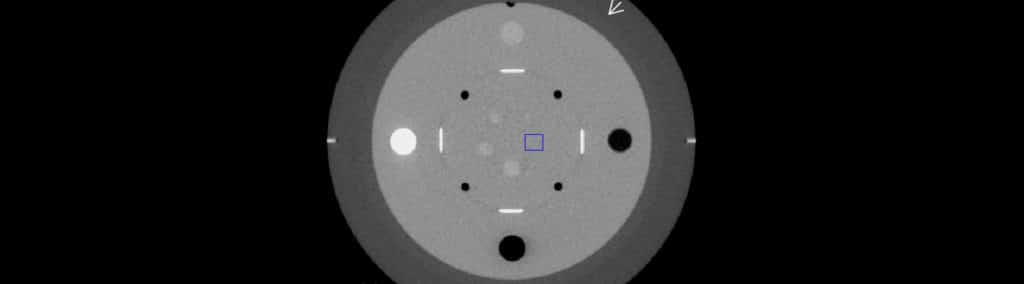

CT Scanner Calibration Artifact – Metrology And Quality News - Online

metrology.news

metrology.news

CT Scanner Calibration – Metrology And Quality News - Online Magazine

metrology.news

metrology.news